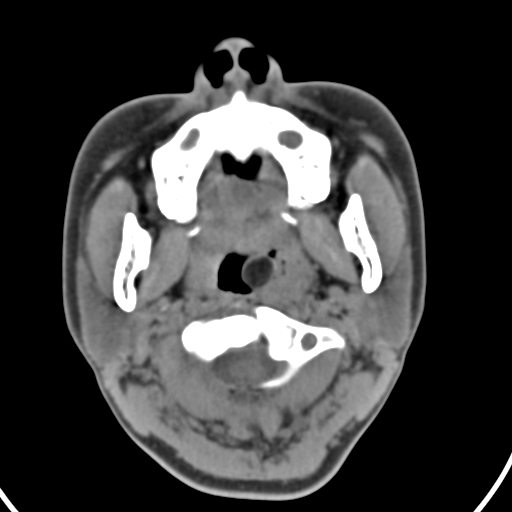

以下是引用zjzjr在2008-12-5 11:46:00的发言:[br]脂肪密度,壁有钙化.考虑口咽部皮样囊肿可能性大.双侧上颌窦炎,双侧下鼻甲粘膜肥厚.增殖腺肥大,扁桃体亦增大,考虑炎性.

以下是引用随光逐影在2008-12-5 18:27:00的发言:[br]1)考虑左侧茎突过长综合征并茎突舌骨韧带囊肿形成突入咽部;左侧咽部慢性炎症。2)鼻咽腺样体肥大。3)双侧扁桃体肿大。4)双侧上颌窦炎。5)双侧下鼻甲粘膜肥厚。